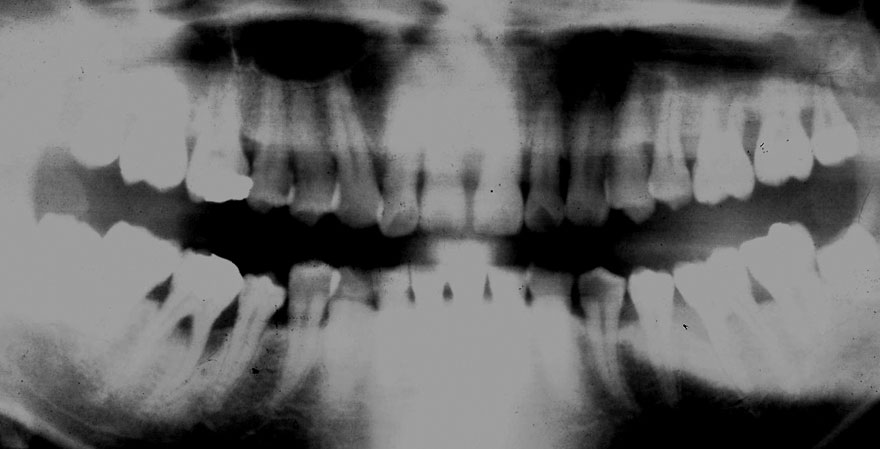

開始年齢 30代

初診時 30歳 女性 平均歯槽骨喪失量:1.46mm

22年後 52歳

平均歯槽骨喪失量:1.55mm

22年間喪失量:-0.09mm

年間喪失速度:-0.004mm

(ケア頻度:1.76ヵ月ごと)